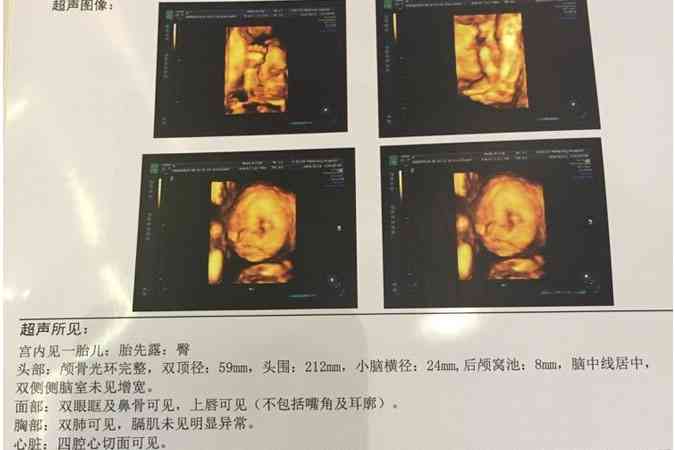

孕期NT檢查可以檢測胎兒頸部的透明帶厚度和鼻骨是否正常,從而評估胎兒是否有患唐氏綜合徵等染色體異常的風險。同時,有些人認為通過NT檢查的圖片可以預測胎兒的性別。特此對於NT圖看男女進行了相關整理,有需要的可以瞭解一下。